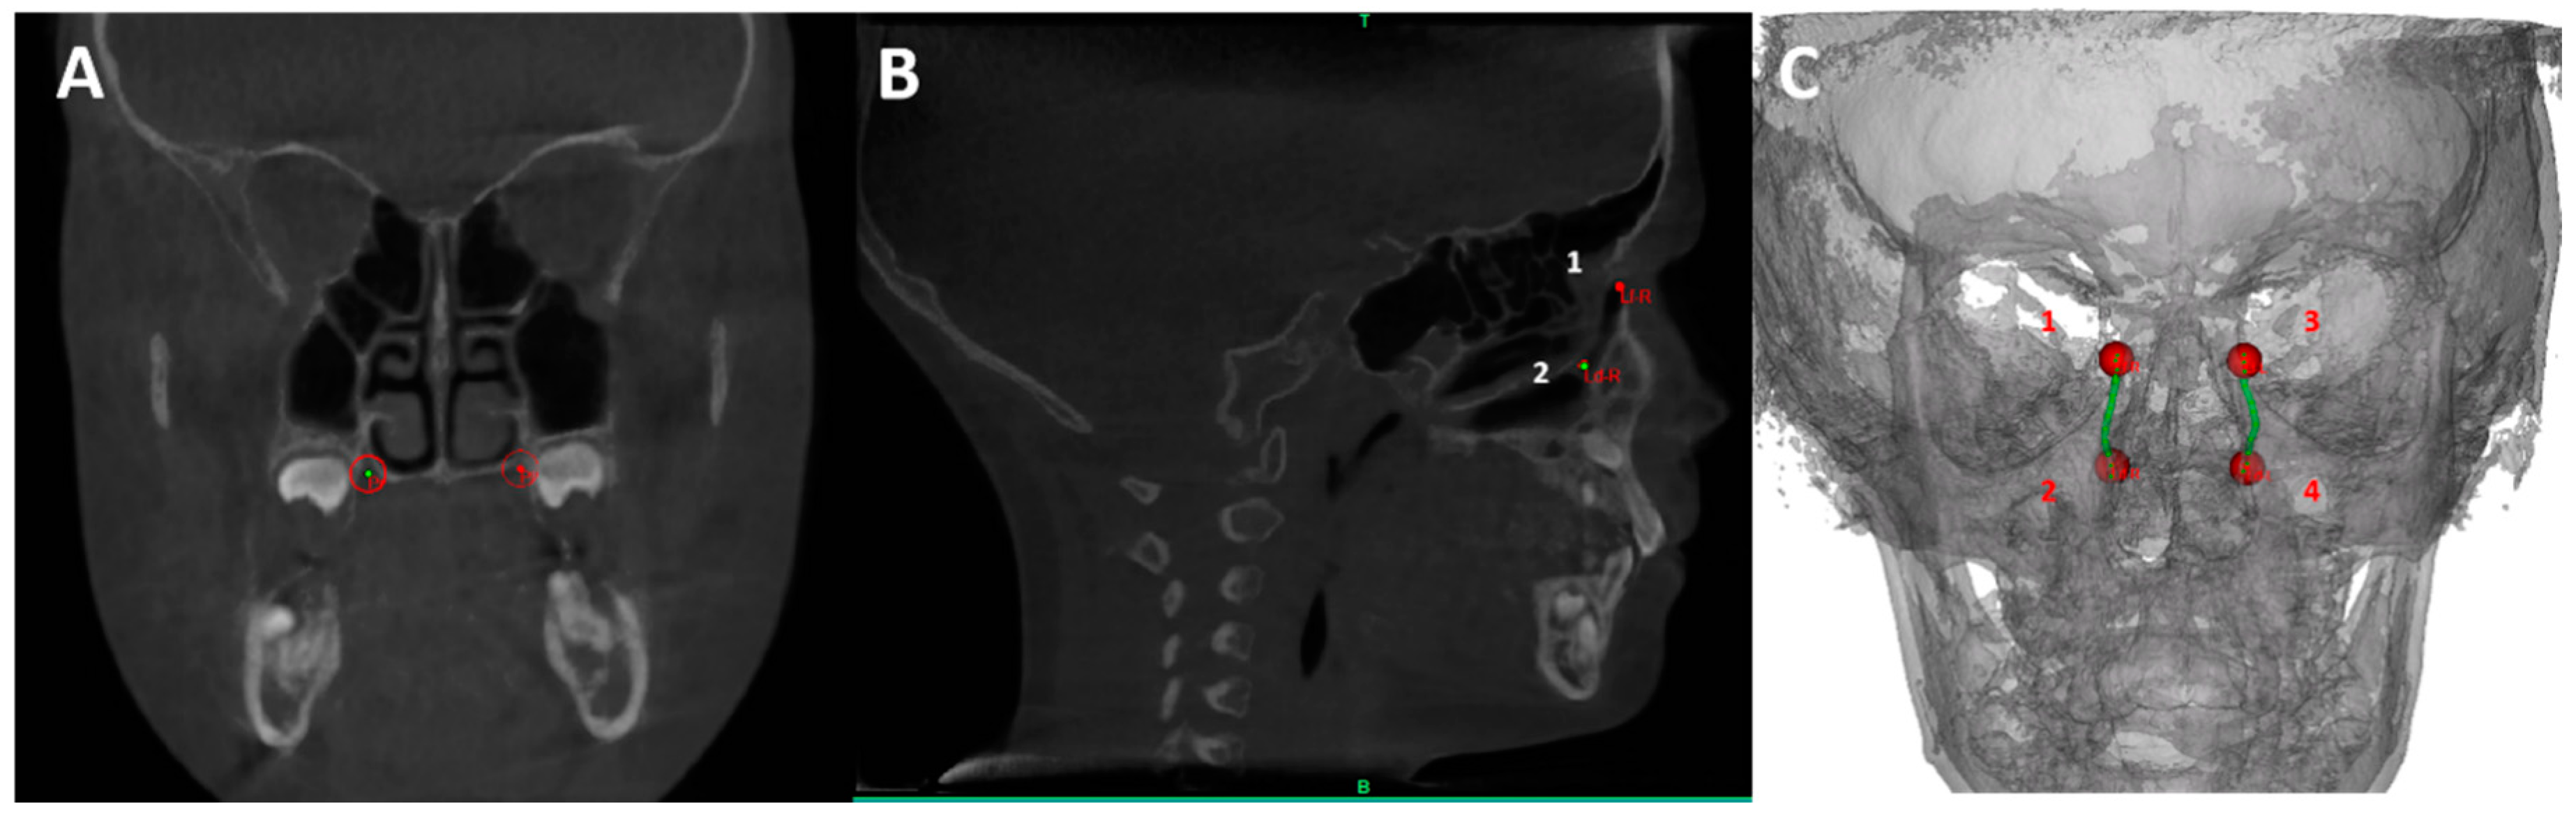

2.7. CBCT

| ANS | The most anterior point on the nasal spine |

| Ba | The most posteroinferior point on the clivus |

| E | Most superior point of the epiglottis |

| LD-L | The most inferior point of the left lacrimal duct |

| LD-R | The most inferior point of the right lacrimal duct |

| LF-L | Centroid of the Lacrimal foramen left |

| LF-R | Centroid of the Lacrimal foramen right |

| MoL | The distal-palatal tip of the first left molar in the upper jaw |

| MoR | The distal-palatal tip of the first right molar in the upper jaw |

| N | The intersection of the internasal and frontonasal sutures in the midsagittal plane |

| Ntip | The tip of the nasal bone |

| OrL | Orbital left, the most inferior anterior point on left orbit’s margin |

| OrR | Orbital right, the most inferior anterior point on right orbit’s margin |

| PNS | The most posterior point on the nasal spine |

| Pl | Centroid of the greater palatine foramen left |

| Pr | Centroid of the greater palatine foramen right |

| PoL | Porion Left: the most upper point on the left bony external auditory meatus |

| PoR | Porion Left: the most upper point on Right bony external auditory meatus |

| S | The midpoint of the sella turcica |

| So | The midpoint of the sella-basion line |

| ii | The point midway between the incisal edges of the maxillary central incisors |

| References Planes | Description |

| Frankfurt plane | A plane passing through the inferior borders of the bony orbits, encompassed by OrR and OrL, and the upper margin of the auditory meatus encompassed by PoL |

| Sagittal SN plane | Plane perpendicular to Frankfurt plane passing through S and N points |

| NTip-ANS plane | Plane through NTip and ANS points, perpendicular to Sagittal SN plane |

| PNS-So plane | Plane through PNS and So points, perpendicular to Sagittal SN plane |

| PNS-Ba plane | Plane through PNS and Ba points, perpendicular to Sagittal SN plane |

| Occlusion plane | Plane through MoL, MoR, and ii points |

| E plane | Plane through E point, parallel to Frankfurt plane |

| NC measurment | |

| NCV | Bounded anteriorly by NTip-ANS plane and posterior by PNS-So plane |

| PA measurments | |

| TPAV | Bounded superiorly by PNS-So plane and inferiorly by E1-E2 plane |

| Miminal CS | The minimal cross-sectional area in Total PA |

| Minimal DH | The minimal hydraulic diameter in Total PA |

| Width | Description |

| Inter lacrimal duct distanct (LD) | Distance between Ld-L and Ld-R |

| Inter lacrimal foramen distance (LF) | Distance between Lf-L and Lf-R |

| Inter-molar distance | Distance between MoL and MoR |

| Palatal width | Distance between Pl and Pr |